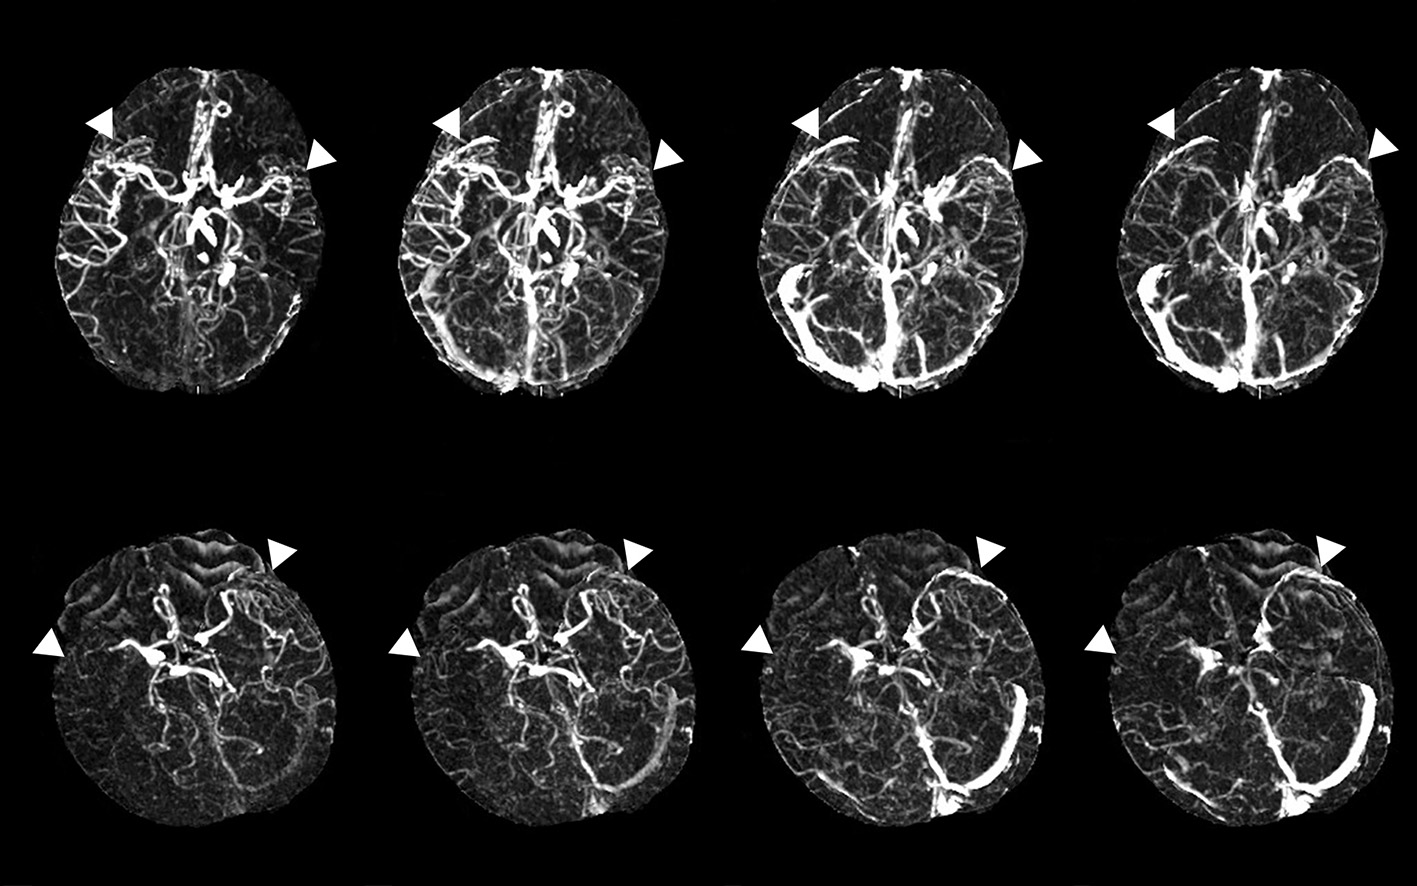

The evaluation of the filling deficit of SMCV involved two types: delayed SMCV and absent SMCV. We defined delayed SMCV as the presence of SMCV filling at the affected side occurring later than that at the contralateral side. Patients who showed absent SMCV filling throughout the arterial phase to the venous phase were marked as absent SMCV (abbreviated as SMCV-) (5) (Figure 1).

Figure 1

Examples of delayed superficial middle cerebral vein (SMCV) (the upper line) and absent filling of the ipsilateral superficial middle cerebral vein (SMCV-) (the lower line). White triangles point to the SMCV.